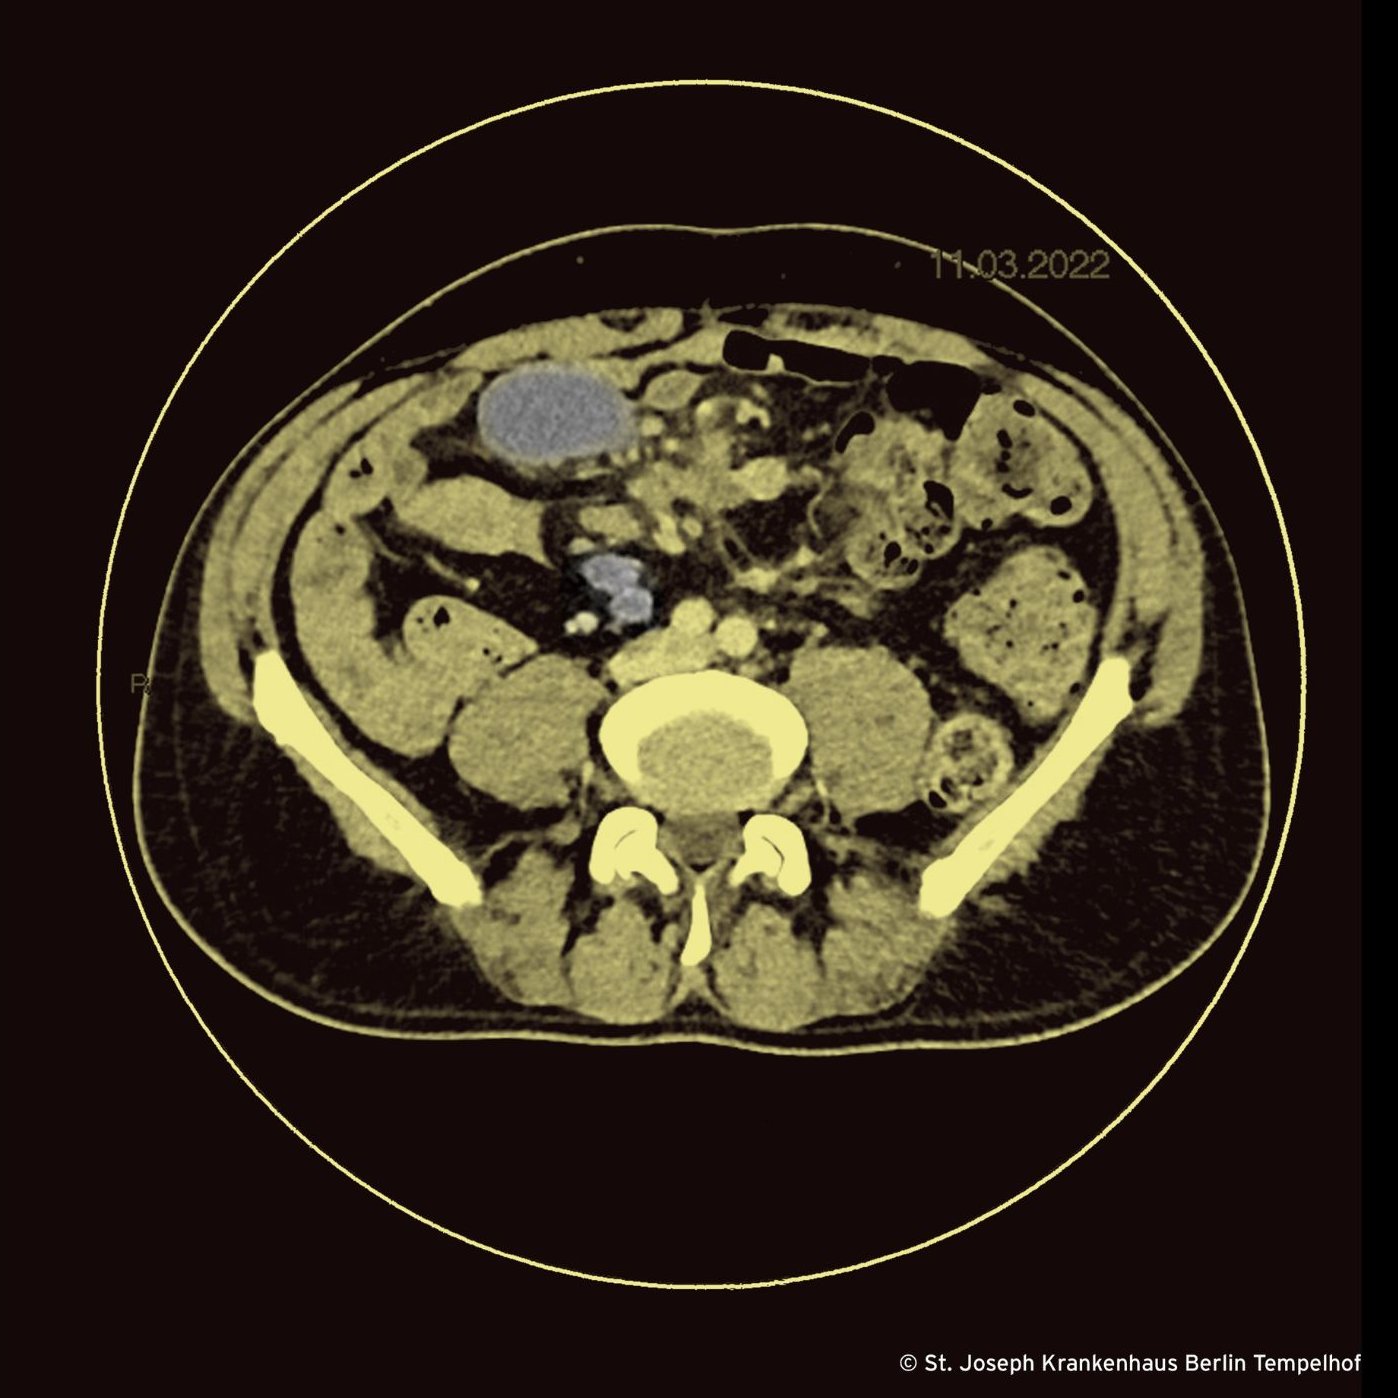

Eineinhalb Monate später – er hat immer noch keine HIV-Medikamente – kommt er ins St. Joseph Krankenhaus mit denselben Beschwerden. Er fühlt sich abgeschlagen, fiebert und verliert weiter an Gewicht. Wir sind uns sicher, es besser zu können. Wir veranlassen eine CT »von Hacke bis Nacke« und warten, wie vor dem Weihnachtsbaum sitzend auf die Röntgendemo. Herr Trübenbach, der Chef unserer Radiologie stellt uns die Bilder mit den Worten vor: »Was auch immer Sie getan haben, Sie haben es gut getan: Die Läsionen in der Lunge sind verschwunden. Im Abdomen sieht es allerdings schlecht aus.« Er zeigt uns viele eingeschmolzene mesenteriale Lymphknoten, von denen wir drei für Sie im Bild farblich gekennzeichnet haben. So weit so gut. Was soll es denn sonst sein? Wir punktieren einen der Lymphknoten und die Mikrobiologin sieht mikroskopisch säurefeste Stäbchen. Über die PCR erfolgt der Nachweis von Mycobacterium tuberculosis-Komplex. Molekularbiologisch finden sich keine Hinweise auf Resistenzen gegen Rifampicin und Isoniazid. Die Kulturen aus der Lungenklinik sind immer noch ohne Wachstum ebenso wie die – noch kurz bebrüteten – Kulturen aus dem Lymphknoten.